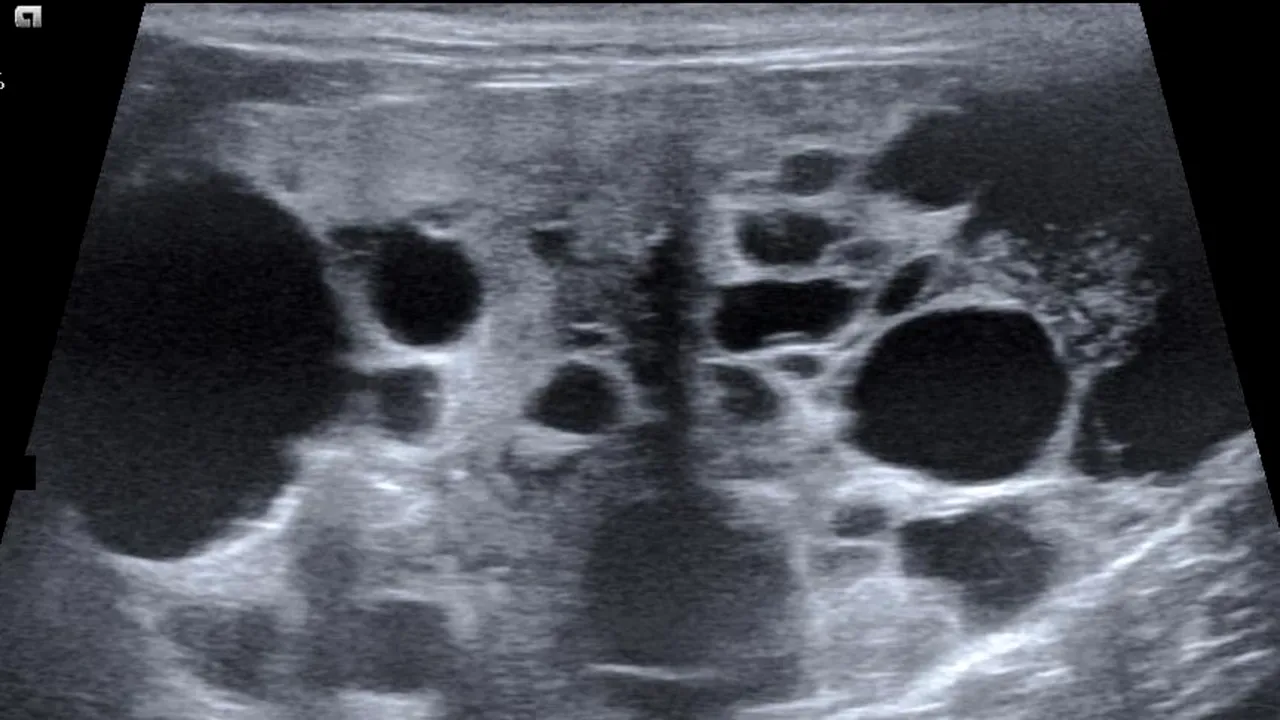

Din cauza durerilor resimțite, a ajuns de urgență la un spital din Mumbai. Când l-au zărit, medicii au bănuit la început că este vorba despre o tumoare. Însă, la operație, au avut un șoc. În interiorul bărbatului era geamănul său, pe care Sanju l-a purtat în pântece vreme de 36 de ani.

„Fetus in fetu” se numește această afecțiune extrem de rară, în care un geamăn este absorbit, dar continuă să preia sângele și nutriția gazdei. Astfel a fost posibil ca geamănului să-i crească dinți, păr, chiar și organe genitale.